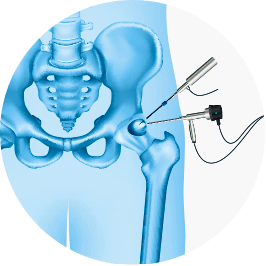

A artroscopia de quadril é um procedimento cirúrgico minimamente invasivo realizado através de pequenas incisões, utilizando-se um aparelho chamado artroscópio para visualizar o interior de uma articulação.